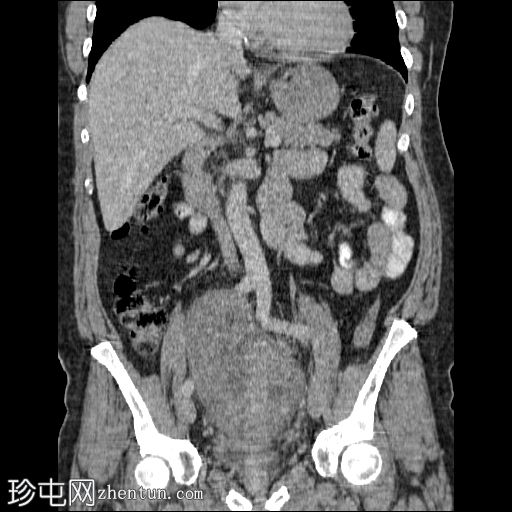

轴位增强扫描(门静脉期)

1.jpg

盆腔内可见一大小为12 x 17 cm的边界清晰的异质性软组织肿块,向下延伸至下腹部。肿块内未见钙化或脂肪密度影。肿块向下推挤膀胱,并牵拉周围肠袢,但无放射学侵犯证据。未见明显淋巴结肿大、腹水或气腹。未见肺部或骨骼局灶性病变。肝脏可见数个小的单纯性囊肿。患者存在少量Bosniak I型肾囊肿,双侧肾盂肾盏系统饱满。曾行胆囊切除术。